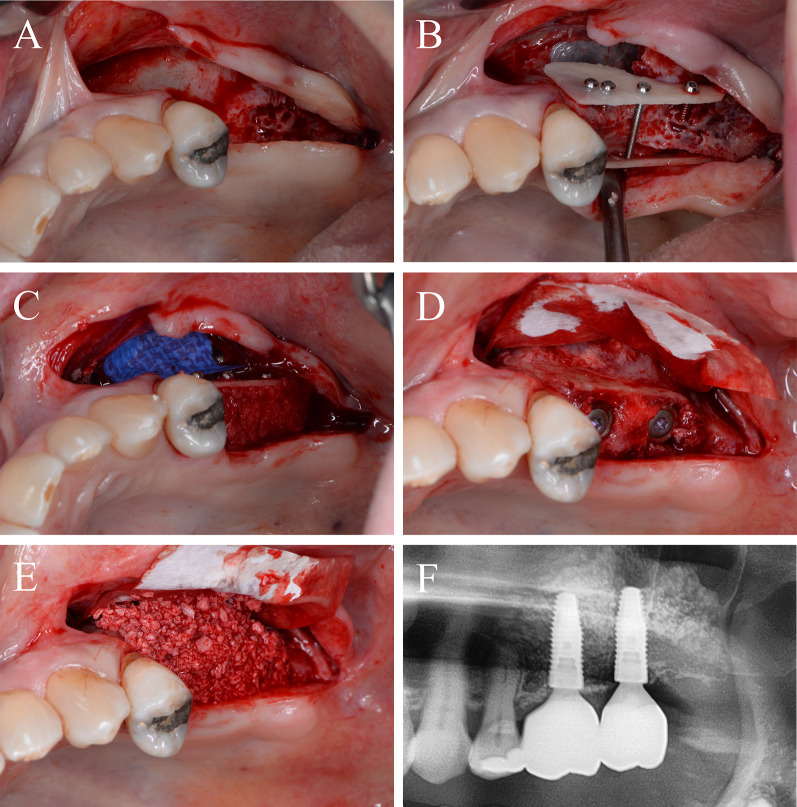

Periodontitis and an extended vertical bone defect of about 4 mm and attachment loss resulted in the loss of the first and second molar of the left maxilla in a 60-year-old patient (Fig. 3A). Surgical procedure included sinus floor elevation of the left sinus by preparing a bone lid and sinus filling using bovine BS. CP was divided into two plates and fixed laterally by two screws (diameter 1 mm) on the buccal and palatinal site of the alveolar crest (Fig. 3B). The space between the CP and the alveolar bone was filled by a layered mixture of autogenous and allogeneic granules. Sinus floor window was covered by a PTFA membrane fixed by two pins (Fig. 3C). After 4 months, screws, PTFA membrane and pins were removed; besides, further edges of the CP were smoothed using a rotating instrument. Then, two bone level tapered implants (BLT, 4.8 × 12 mm, Straumann) were inserted in a sufficient bone volume (Fig. 3D). After implant placement, a granular bovine BS was used to cover the augmented area to prevent resorption (relining) and covered by a porcine pericardium membrane (Fig. 3E). Four months after healing, implants were uncovered and gingiva formers were installed along with a roll flap in order to increase the thickness of the keratinized peri-implant mucosa. After one month of healing, the implants were provided with single crowns by the referring general dentist (Fig. 3F). Within the follow-up of 16 months, the case remained stable without complications.

Fig. 3.

Alveolar ridge augmentation of the posterior maxilla. A Initial intraoperative situation with an extended alveolar defect of the posterior alveolar jaw. B Intraoperative situation after sinus floor elevation and fixation of two allogeneic cortical bone plates buccal and palatinal using four fixation screws. C Intraoperative situation after filling sinus floor with xenogeneic bone substitute, covering it with PTFE matrix and filling the alveolar crest with allogeneic spongious granules. D After 4 months, sufficient bone remodeling, screws removed, and implants inserted. E Overlining with xenogeneic granules for resorption protection and covered by collagen matrix. F X-ray demonstrating inserted implants